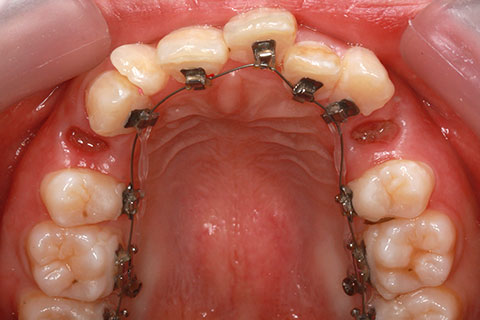

矯正期間24ヶ月

ハーフリンガル矯正3(上の歯のみ舌側矯正で治療)

治療前

治療中(開始直後)

治療中(開始半年後)

治療後

- 年齢・性別

- 25歳女性

- 治療期間

- 2年0ヶ月

- 抜歯

- 上下4番抜歯

- 治療費

- 110万円

- 備考

- 治療内容

- 施術の副作用(リスク)

- 表側矯正と比較して、力学的な操作性が複雑なため、ボーイングエフェクトを起こしやすい。